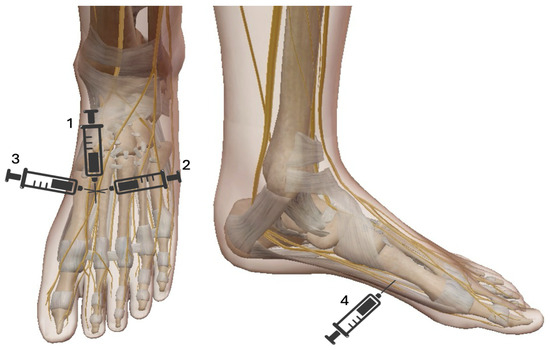

3. Innervation of the Foot and Ankle

The sensory and motor innervation of the foot and ankle is primarily derived from the sciatic and saphenous nerves, branches of the lumbosacral plexus. The sciatic nerve (roots L4-S3) descends through the posterior thigh and bifurcates in the popliteal fossa into the tibial and common peroneal nerves [7]. The tibial nerve descends and passes posterior to the medial malleolus before branching into medial and lateral plantar nerves. The plantar nerves provide sensory innervation to the sole of the foot, and the intrinsic muscles of the foot (e.g., flexor digitorum brevis and abductor hallucis). Specifically, the medial plantar nerve innervates the medial two-thirds of the sole of the foot, and the lateral plantar nerve innervates the lateral third and the small muscles of the foot [2]. The common peroneal nerve wraps around the fibular neck after branching from the sciatic nerve and then derives into the deep peroneal nerve (DPN) and superficial peroneal nerve (SPN). DPN is responsible for motor innervation to the muscles of the anterior compartment of the leg (e.g., tibialis anterior) and sensory innervation to the interdigital space between the first and second toes. SPN provides sensation to the dorsum of the foot and the lateral part of the lower leg and provides motor innervation to the peroneus longus and brevis muscles. The medial side of the foot and ankle are also innervated by the saphenous nerve (sensory branch of the femoral nerve), which is the longest branch of the femoral nerve running along the great saphenous vein. It provides cutaneous sensation to the medial leg, ankle and foot. A comprehensive understanding of this intricate anatomy is essential for effective regional anesthesia, as it allows precise targeting of the nerves responsible for sensory and motor function in the surgical area, optimizing perioperative pain management.

Innervation of foot and ankle is resumed in Figure 1.

A synthesis of foot and ankle innervation, organized by cutaneous, muscular, and bony structures.

Figure 1. Innervation of foot and ankle.